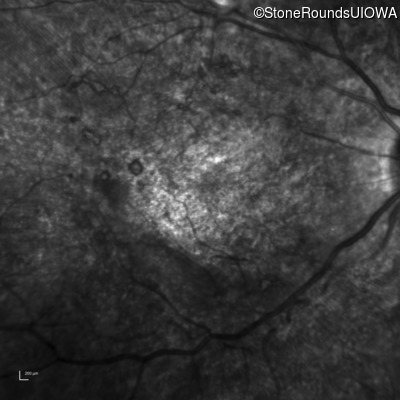

Infrared Fundus Photograph - Left - 20/250 sc

Exemplar